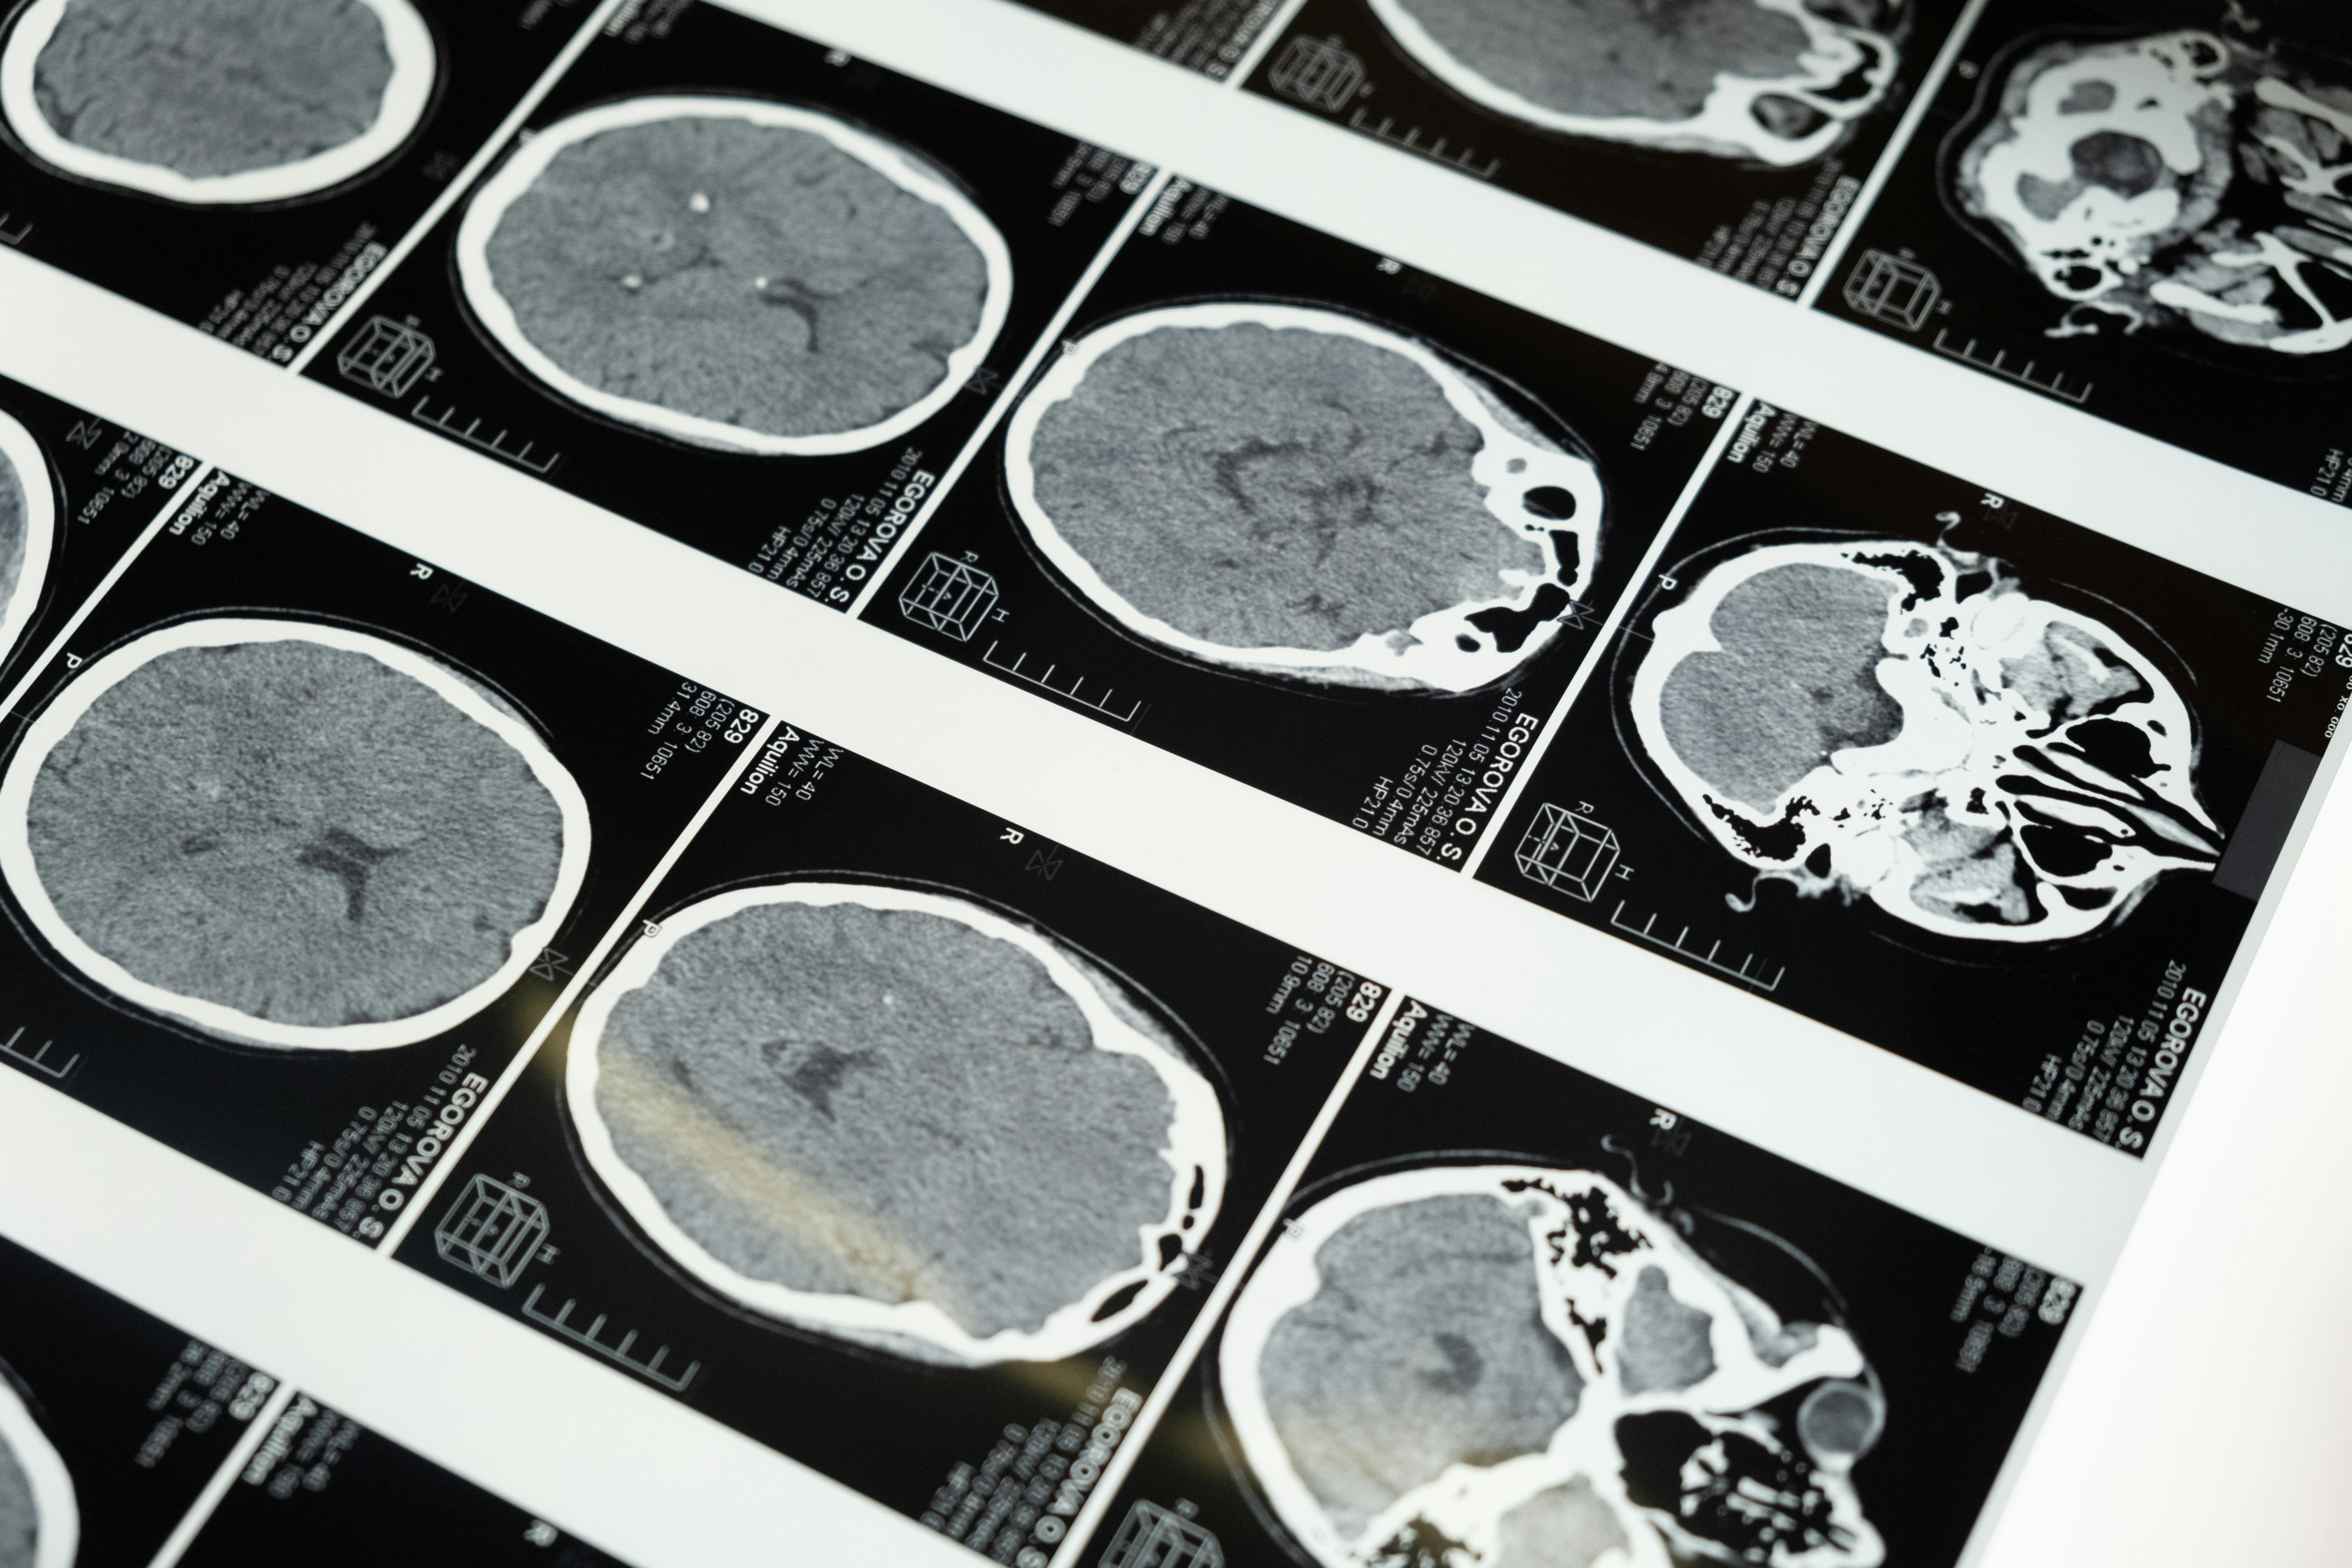

알츠하이머병은 여러 단계로 나뉘어져 있어요. 초기에는 최근 기억의 감소가 나타나고, 점차 언어 사용의 어려움, 일상 생활의 어려움으로 발전해요. 마지막 단계에서는 심각한 인지 장애와 행동 문제까지 발생할 수 있어요.

| 알츠하이머 치매 | 단계별 증상 |

| 1단계 | 최근 기억 감퇴 |

| 2단계 | 같은 말 반복 등 언어 능력 저하 |

| 3단계 | 집안일, 취미 활동 불가능 |

| 4단계 | 밤낮, 계절, 연도 구분 불가능 |

| 5단계 | 우울증, 공격성 망상증 심화 |

| 6단계 | 대소변 실금, 보행장애 |